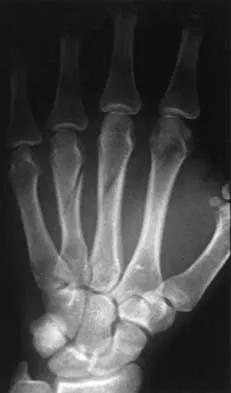

Question 66

A 23-year-old woman sustains an injury to her right hand after falling off her snowboard. Examination reveals that she has difficulty moving her fingers. A radiograph and a clinical photograph are shown in Figures 8a and Figure 8b. Management should consist of

Explanation

The radiograph reveals oblique fractures of the third and fourth metacarpals. The rotational component of the fracture displacement is well visualized on the clinical photograph, which shows scissoring of the middle finger over the ring finger. The fracture obliquity results in rotational deformity that cannot be adequately maintained and held by closed treatment. The treatment of choice is open reduction and internal fixation. Stern PJ: Fractures of the metacarpals and phalanges, in Green DP, Hotchkiss RN, Pederson WC (eds): Green's Operative Hand Surgery, ed 4. Philadelphia, PA, 1999, pp 711-771. Freeland AE, Benoist LA, Melancon KP: Parallel miniature screw fixation of spiral and long oblique hand phalangeal fractures. Orthopedics 1994;17:199-200.